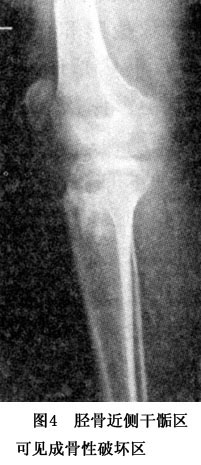

X線表現,包括以下3個方面:①原來的骨皮質和髓腔的破壞,即骨的溶解;②鈣化和骨形成;③骨膜下新骨形成。在骨肉瘤的早期,X線上只有一些微小的異常,但在患者初診時,其X線表現往往已經很明顯了。骨肉瘤的X線表現是多種多樣的,在很大程度中取決於腫瘤所產生骨的多少。在X線平片上,骨肉瘤表現爲硬化型、溶骨型或混合型。溶骨和骨硬化同時存在的混合型骨肉瘤最常見(圖3,4),而單純溶骨型或骨硬化型相對較少。單純溶骨主要是血管擴張型骨肉瘤的特點。四肢管狀骨的典型骨肉瘤位於幹骺區髓內,邊界不清,可以侵破皮質,形成巨大的軟組織腫塊。可以見到Codman三角(圖5),或日光放射樣骨膜反應,有時也可以出現病理骨折。發生於長骨骨幹處的骨肉瘤可以表現爲骨硬化性病竈和內骨膜增厚,而無皮質破壞或骨膜炎(periostitis)。發生於骨骺部的骨肉瘤通常爲溶骨性病變。肌腱和韌帶經常是腫瘤蔓延生長的橋樑。